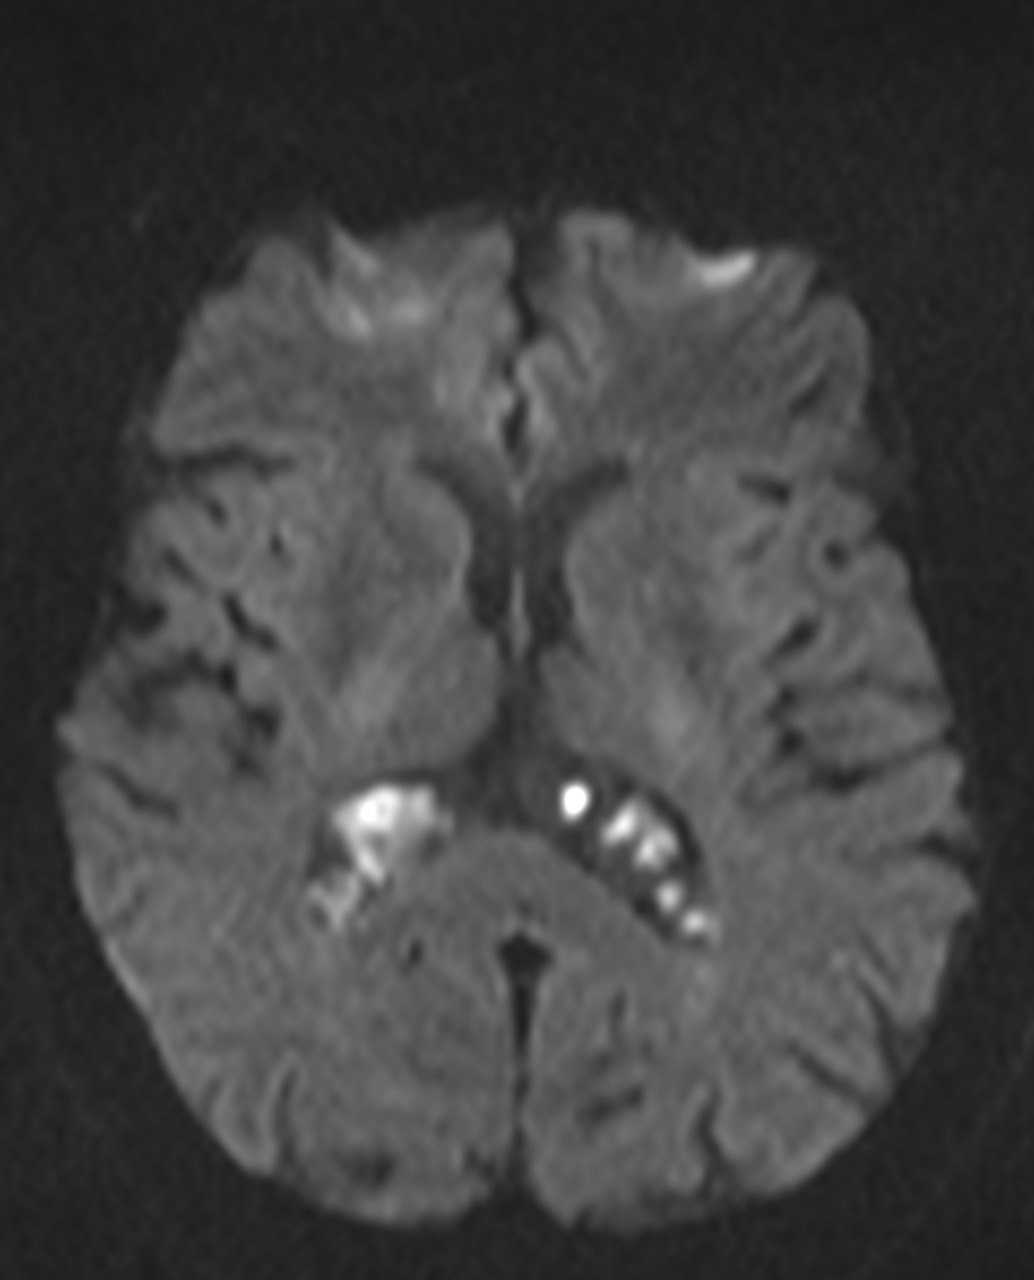

Son pseudolesiones frecuentemente observadas en estudios de neuroimagen.

Sus principales características son:

✔ Lesiones intraventriculares

✔Bilaterales

✔65% restringen en la secuencia de difusión

✔ Realce variable posterior a la administración de medio de contraste

✔ No hay edema del parenquima adyacente

NO DEBEN CONFUNDIRSE CON LESIONES TUMORALES INTRAVENTRICULARES!!!!